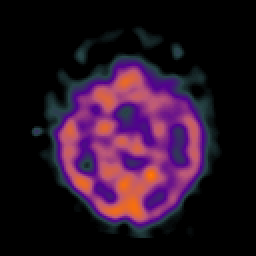

AIDS dementia: overlay -- Slice #7

[Home][Help][Clinical][Tour 1] Slice 7